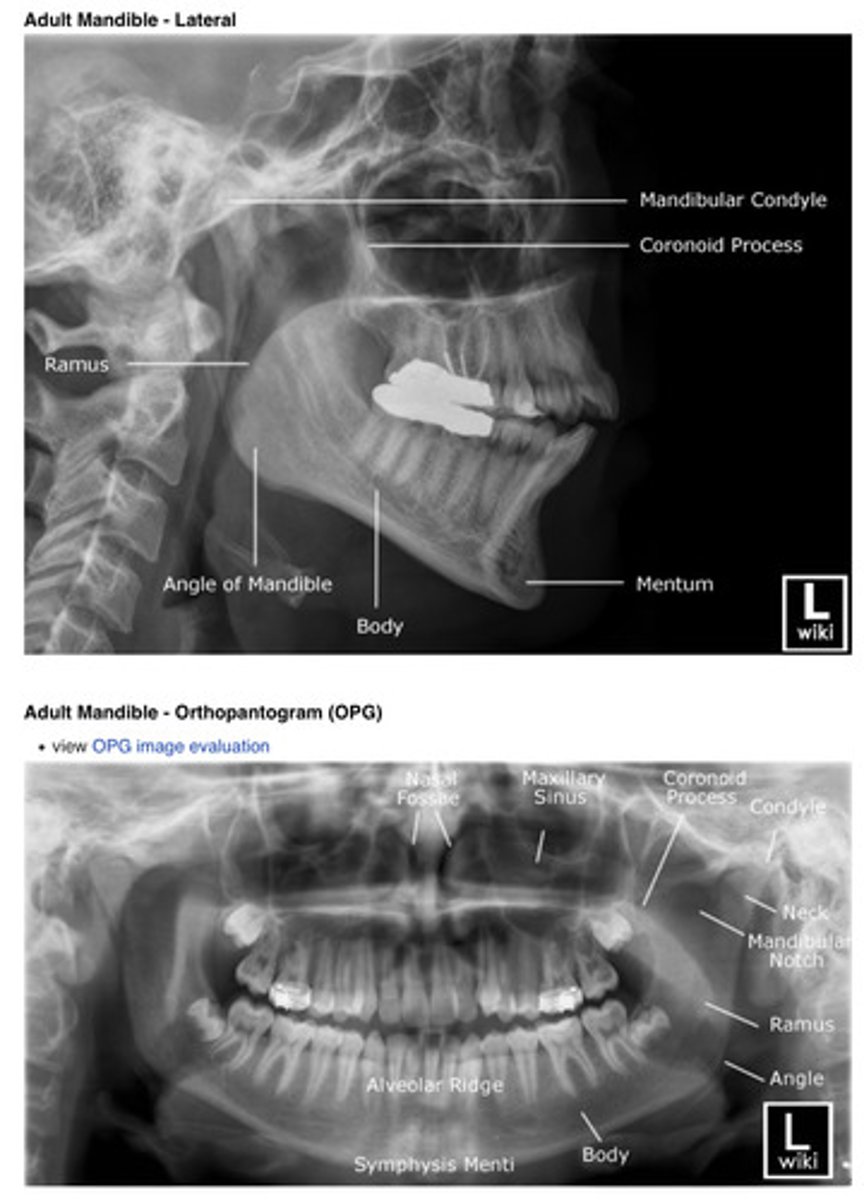

Simple diagram of the teeth:

Example of an adult OPG x-ray: